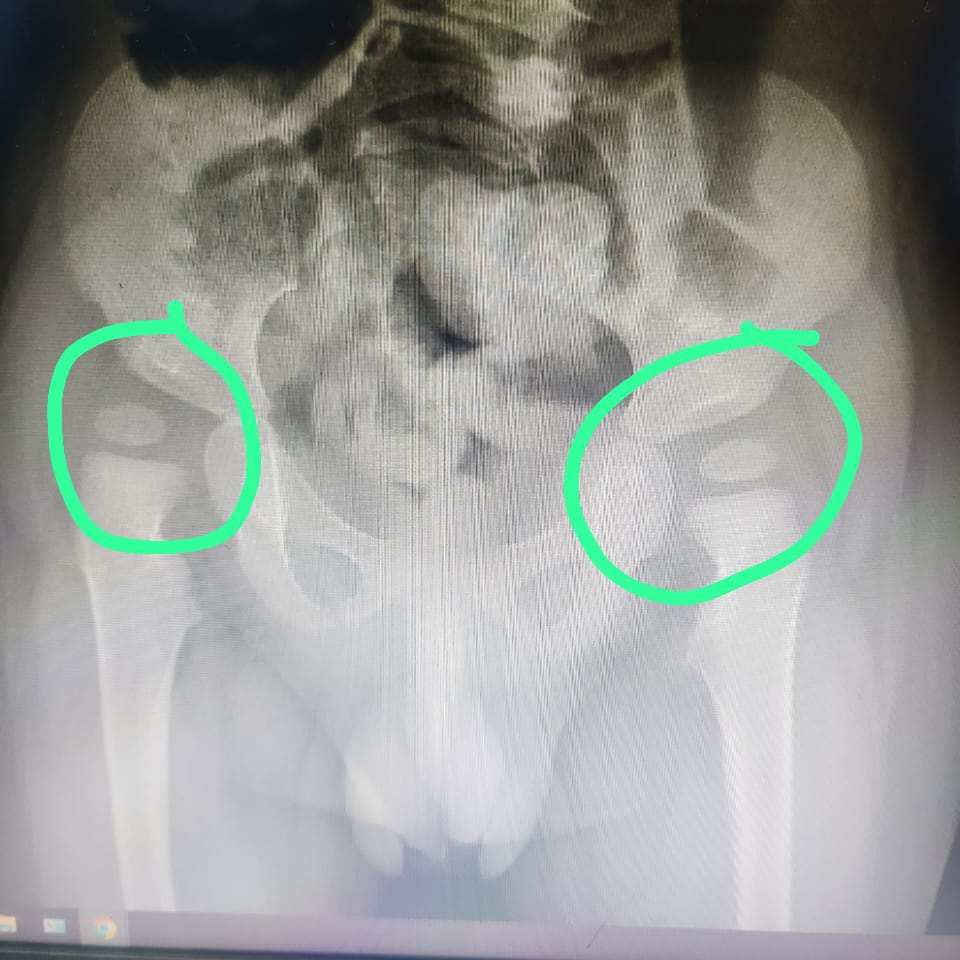

Saat usianya 8 bulan, Ryuga sudah didiagnosa kerusakan otak yang membuatnya tidak bisa mengontrol gerakan tubuh dan ototnya (Cerebral Palsy), serta didiagnosa infeksi pada bagian belakang tenggorokannya (Faringo).

Tubuh anakku menjadi kaku dan ia sulit bernapas. Di usianya yang sekarang, ia hanya bisa terbaring lemah. Bahkan sekedar untuk tertawa saja belum bisa. Setiap hari aku menanti keajaiban, berharap suatu hari ia bisa tertawa lepas dan bahagia.

Saat usianya 8 bulan, Ryuga sudah didiagnosa kerusakan otak yang membuatnya tidak bisa mengontrol gerakan tubuh dan ototnya (Cerebral Palsy), serta didiagnosa infeksi pada bagian belakang tenggorokannya (Faringo).

Tubuh anakku menjadi kaku dan ia sulit bernapas. Di usianya yang sekarang, ia hanya bisa terbaring lemah. Bahkan sekedar untuk tertawa saja belum bisa. Setiap hari aku menanti keajaiban, berharap suatu hari ia bisa tertawa lepas dan bahagia.